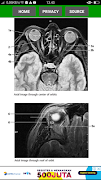

The key for any beginning radiologist who wishes to recognize pathological findings is to first acquire an ability to distinguish them from normal ones. This outstanding guide gives beginning radiologists the tools they need to systematically approach and recognize normal MR and CT images.

* Reference-quality images from the author's own teaching files show all standard normal findings as seen in CT and MRI

*Checklists in each section offer the reader a systematic way to approach the images

*Lists of standard measurements and tips for ruling out pathology